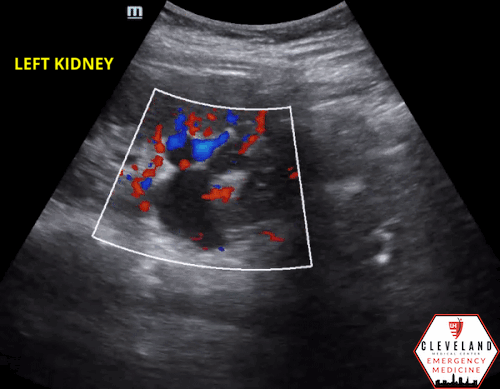

8. Apply color doppler to the kidney, particularly over the renal pelvis, to differentiate vasculature from hydronephrosis.

Pitfalls

Hydronephrosis can commonly be confused with the medullary pyramids of the kidneys, as well as cysts or vascular prominence/malformation. Pyramids and renal cysts are distinct structures and tend to be more peripherally located compared to hydronephrosis which starts centrally. Vasculature can be differentiated from hydronephrosis with color doppler [5-7].